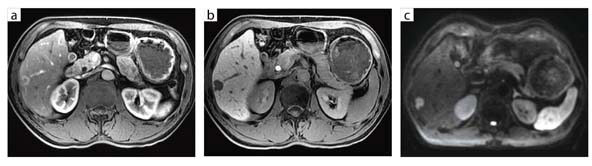

図1 B型慢性肝炎に生じた肝細胞がん(32chボディアレイコイル)

a:LAVA-FLEX(脂肪抑制画像),ダイナミックスキャンの第1フェイズ

b:LAVA-FLEX(脂肪抑制画像),肝細胞相,スライス厚 3.6mm

c:DWI,b値800,スライス厚 5mm,呼吸同期法

谷本:Discovery MR750には,ピクセルごとの局所磁場不均一を計算して再構成することでアーチファクトを抑制する“LAVA-FLEX”というパルス系列が搭載されていますが,肝臓撮像時にLAVA-FLEXを使用することで,きわめて高画質が得られています。1.5Tで使用していたLAVAと比較すると,脂肪がより均一に抑制されますので,造影検査においては非常に有利ですし,T2強調画像でも画質が大幅に向上しています。

また,肝臓の撮像時に最も大事なのはスライス厚とマトリックス数ですが,1.5Tでは,スライス厚を薄くしてマトリックス数を増やすとS/Nはかなり低下してしまいます。しかし,3Tの場合はもともとS/Nが高いため,スライス厚を薄くしてもマトリックス数が増やせるわけです。

拡散強調画像については, 3Tでは1.5Tよりも描出能が低下するというのが一般的な見方でした。しかし,Discovery MR750の場合,1.5TよりもはるかにS/Nの高い明瞭な画像が撮像できる機会が増えました。当院では現在,肝臓の拡散強調画像は5mmスライス厚で撮像していますが,2〜3mm程度の転移も見つかるようになりました。また,当院の場合b値は,1.5Tでは肝臓は600,膵臓は1000に設定しています。しかし3Tでは,高いS/Nを生かして,肝臓も膵臓もb値を1000に設定しました。これにより,正常組織の信号が抑制されてコントラスト分解能が向上し,T2 shine-throughが減少するというメリットが得られています。

1.5Tと3Tでは,T1コントラストの違いも当初は指摘されていましたが,Discovery MR750では1.5Tとまったく変わらず,むしろ向上しています。

谷本:体幹部の撮像は,基本的にはすべて32chボディアレイコイルを使用しています。上腹部と骨盤部が同時にスキャンできますので,特に特殊検査では非常に有利です。例えば,尿路の撮像では,腎臓から膀胱までを一度にスキャンしますが,広範囲でも磁場均一性に優れた高空間分解能画像が得られるようになりました。

また,肝臓検査において,当院では,MRIは最終診断法に位置付けています。MRIは被ばくもないですし,コントラスト分解能はCTよりも圧倒的に高いので,CTで鑑別がつかない場合に一歩進めた診断ができます。その際,3T MRIで1.5T MRIよりも高い診断能を得るために,32chボディアレイコイルとLAVA-FLEXの組み合わせは強力な武器となります。RF送信のドライブポイント(給電点)が4つある“4ポイントドライブ”という新技術によってRFのペネトレーションが向上し,高い磁場均一性が得られるため,当院では誘電パッドをまったく使用せずに撮像できています。